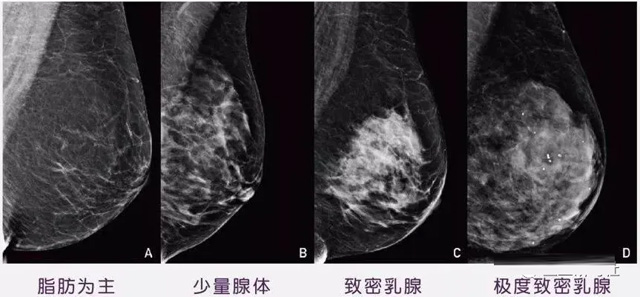

女性乳腺的自我檢查,特別是注意有小結(jié)節(jié),腫塊,乳頭有液體滲出情況,需要通過乳腺DR,X光線,磁共振等影像技術(shù)檢查。胸的大小跟乳腺癌沒多大關(guān)系,乳腺的密度大發(fā)病率高一些,胸小脂肪少致密性大。更容易乳腺癌。這個還不能通過自我檢查來確認。致密乳腺組織看上去是白色或淺灰色需要通過乳腺X射線檢查。

乳腺X射線有輻射,40歲以下的女性沒有高危因素跟臨床特征,醫(yī)生都是不建議使用鉬靶檢查。乳腺超聲無創(chuàng)無輻射,對乳腺組織分辨率高??梢詫⑷橄倌[塊從致密型乳腺組織中輕松查出來,多普勒模式檢查乳腺及病變,超聲小于1厘米的病灶非腫塊性乳腺癌檢出率低。超聲檢查結(jié)果依賴醫(yī)生水平和經(jīng)驗,乳腺DR超聲推動乳腺超聲圖像的標準化,提高檢查的準確率。對乳腺組織內(nèi)的細小鈣化灶, 從范圍、乳腺X射線形態(tài)以及分布特點上進行定性診斷。造影劑增強型乳腺X線攝影靜脈注射碘化造影劑結(jié)合乳房X線攝影。磁共振MRI對乳腺癌研究的深入對軟組織具有較高的分辨率等特點,在臨床上被廣泛認可。乳腺CT的探測器圍繞著乳房成像,無痛無擠壓,3D乳房圖像乳腺病灶的大小、數(shù)量、形狀、位置以及血管分布。一次掃描可創(chuàng)建多達兩千張投影圖像 。乳腺PET,適合普通人群和乳腺癌高危人群早期檢測,發(fā)現(xiàn)極早期微小病灶并明確定性。